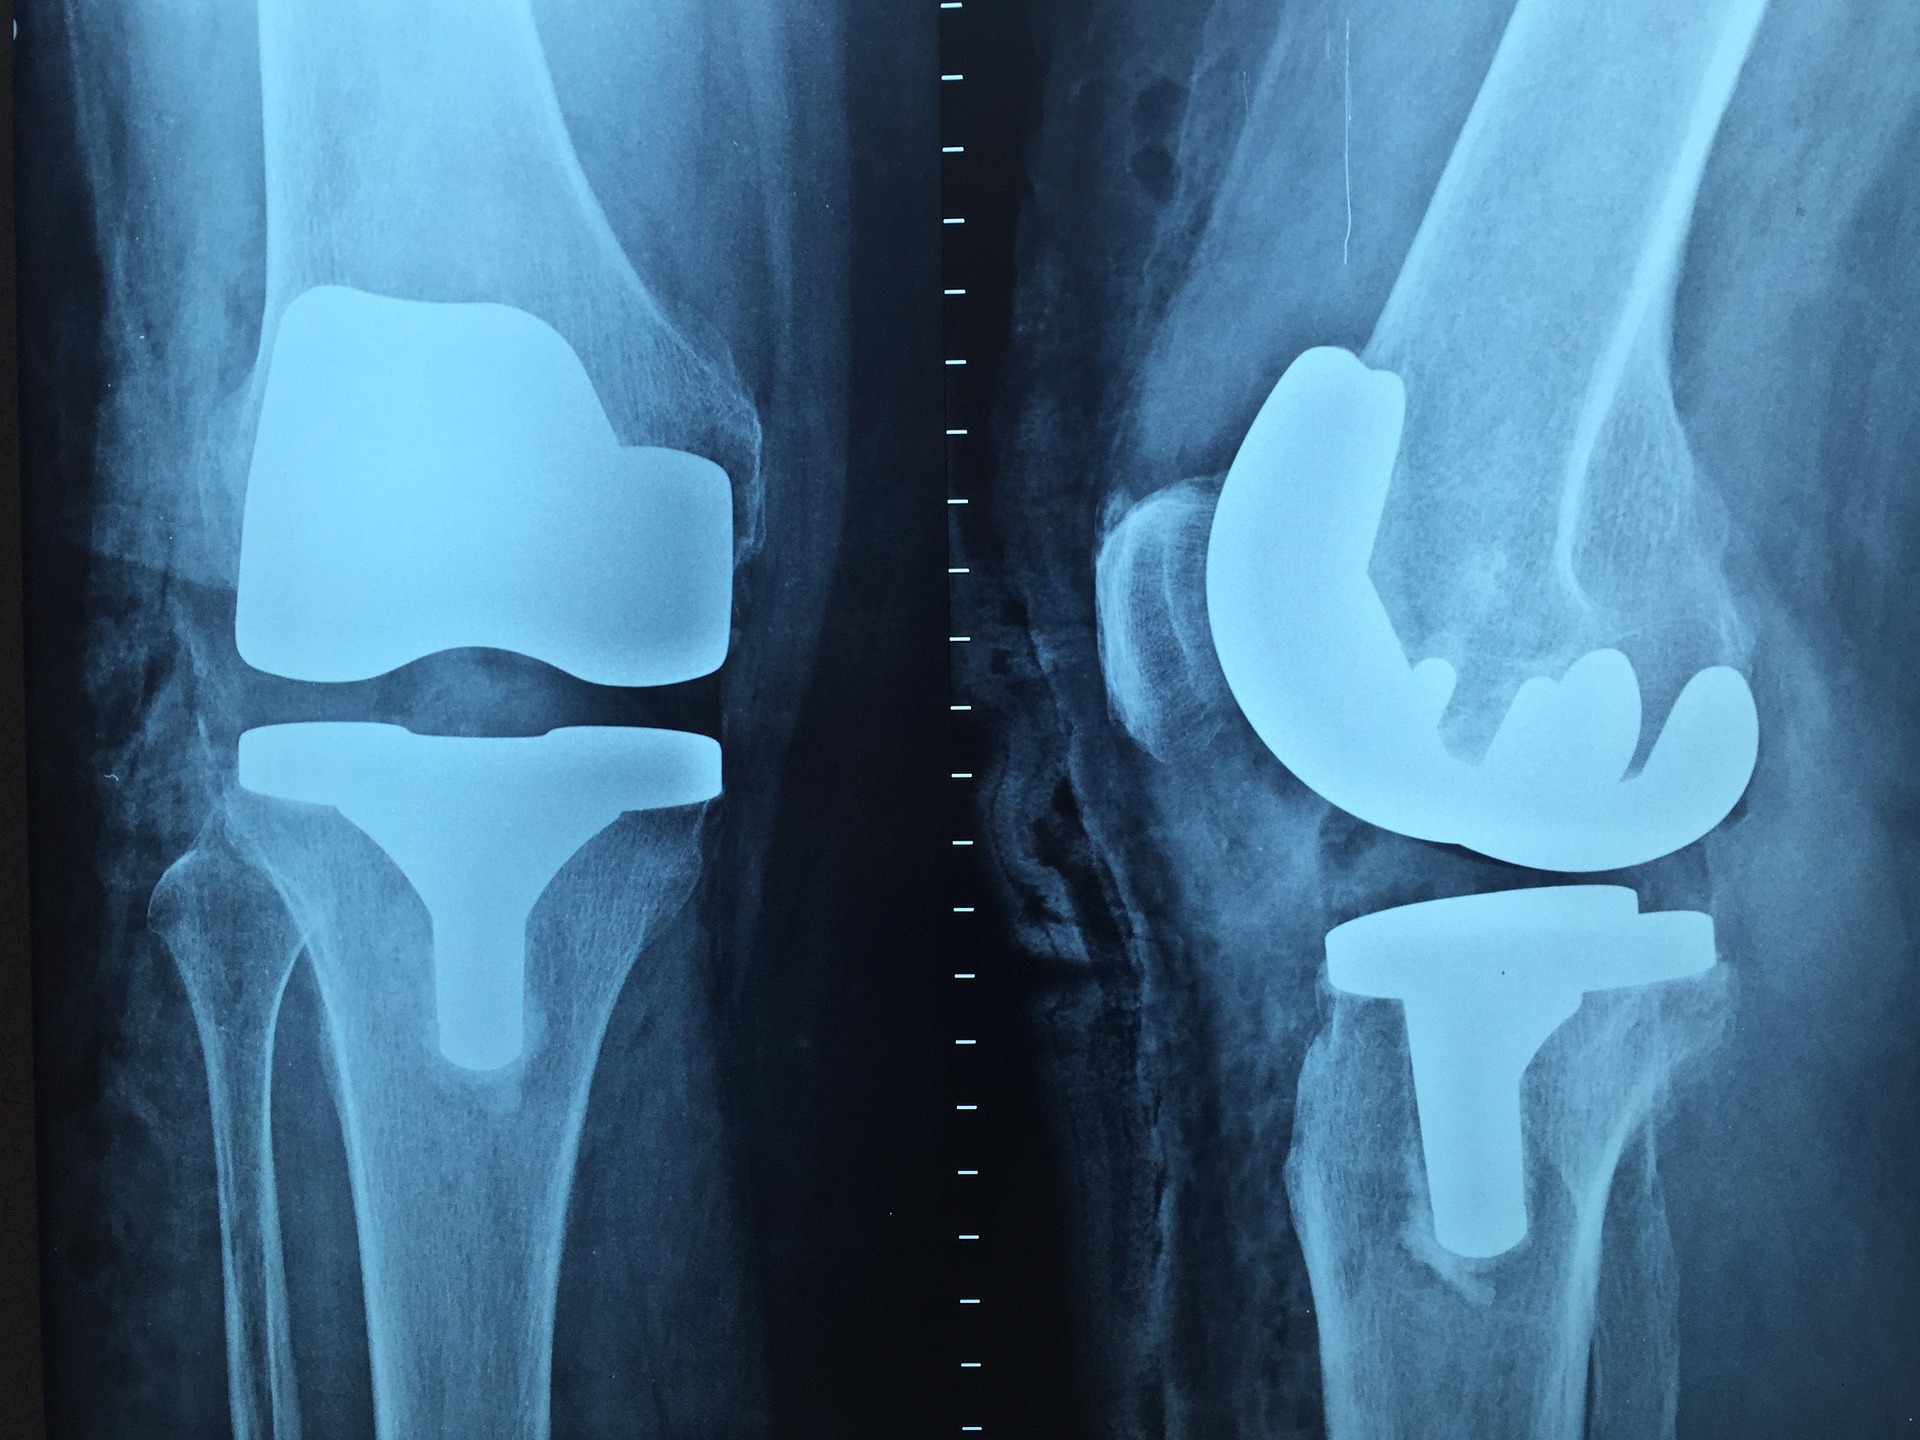

Prześwietlenie kończyn wykonuje się w przypadku urazów, deformacji lub bólu po upadkach. Jest to jeden z najstarszych i najskuteczniejszych sposobów oceny struktur kostnych. Laryngolog może skierować na prześwietlenie zatok, które pomaga różnicować przyczyny przewlekłych bólu lub niedrożności.

Stomatologiczne RTG jest odrębną kategorią, ponieważ służy ocenie zębów i struktur okołozębowych. Takie obrazowanie jest istotne przed zabiegami chirurgicznymi lub w przypadkach przewlekłych procesów zapalnych. Wynik każdego z badań opisuje radiolog, co stanowi podstawę do dalszych decyzji klinicznych.